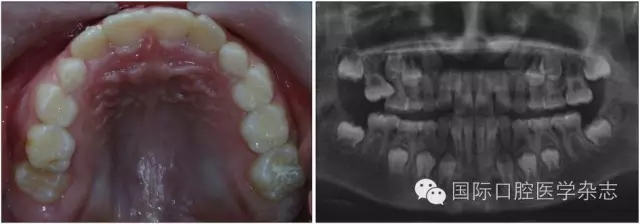

圖3為一因“乳磨牙爛牙”前來就診兒童的X線片檢查。影像學(xué)檢查顯示:第二乳磨牙近中深齲,近遠中牙根吸收均不明顯,但遠中根尖病變引起了第二前磨牙萌出方向的改變。臨床處置:及時拔除了齲壞的第二乳磨牙,制作第一恒磨牙帶環(huán)絲圈間隙維持器,3個月后復(fù)診,X線片顯示第二前磨牙萌出方向逐漸正向調(diào)整;6個月后復(fù)診,第二前磨牙基本正位萌出;1年后復(fù)診,第二前磨牙調(diào)整到位。從圖3的病例可以看出:乳磨牙根尖周病變會引起恒牙萌出方向的改變,出現(xiàn)咬合紊亂的潛在性表現(xiàn),但臨床上通過去除病灶牙與簡單的間隙維持、未實施牽引助萌即糾正了該病例潛在性的咬合紊亂發(fā)生。

A:下頜第二乳磨牙近中齲,X線片顯示遠中根尖周病變引起繼承恒牙萌出方向改變;B:擬及時拔除病變的下頜第二乳磨牙,行間隙維持;C:拔除病變的下頜第二乳磨牙間隙維持后一段時間,繼承恒牙萌出方向發(fā)生正向改變;D:繼承恒牙正位萌出。

圖3 乳牙根尖炎癥引起繼承恒牙萌出方向改變的典型病例

Fig 3 Typical case oferuptive direction change caused by periapical infection of primary tooth